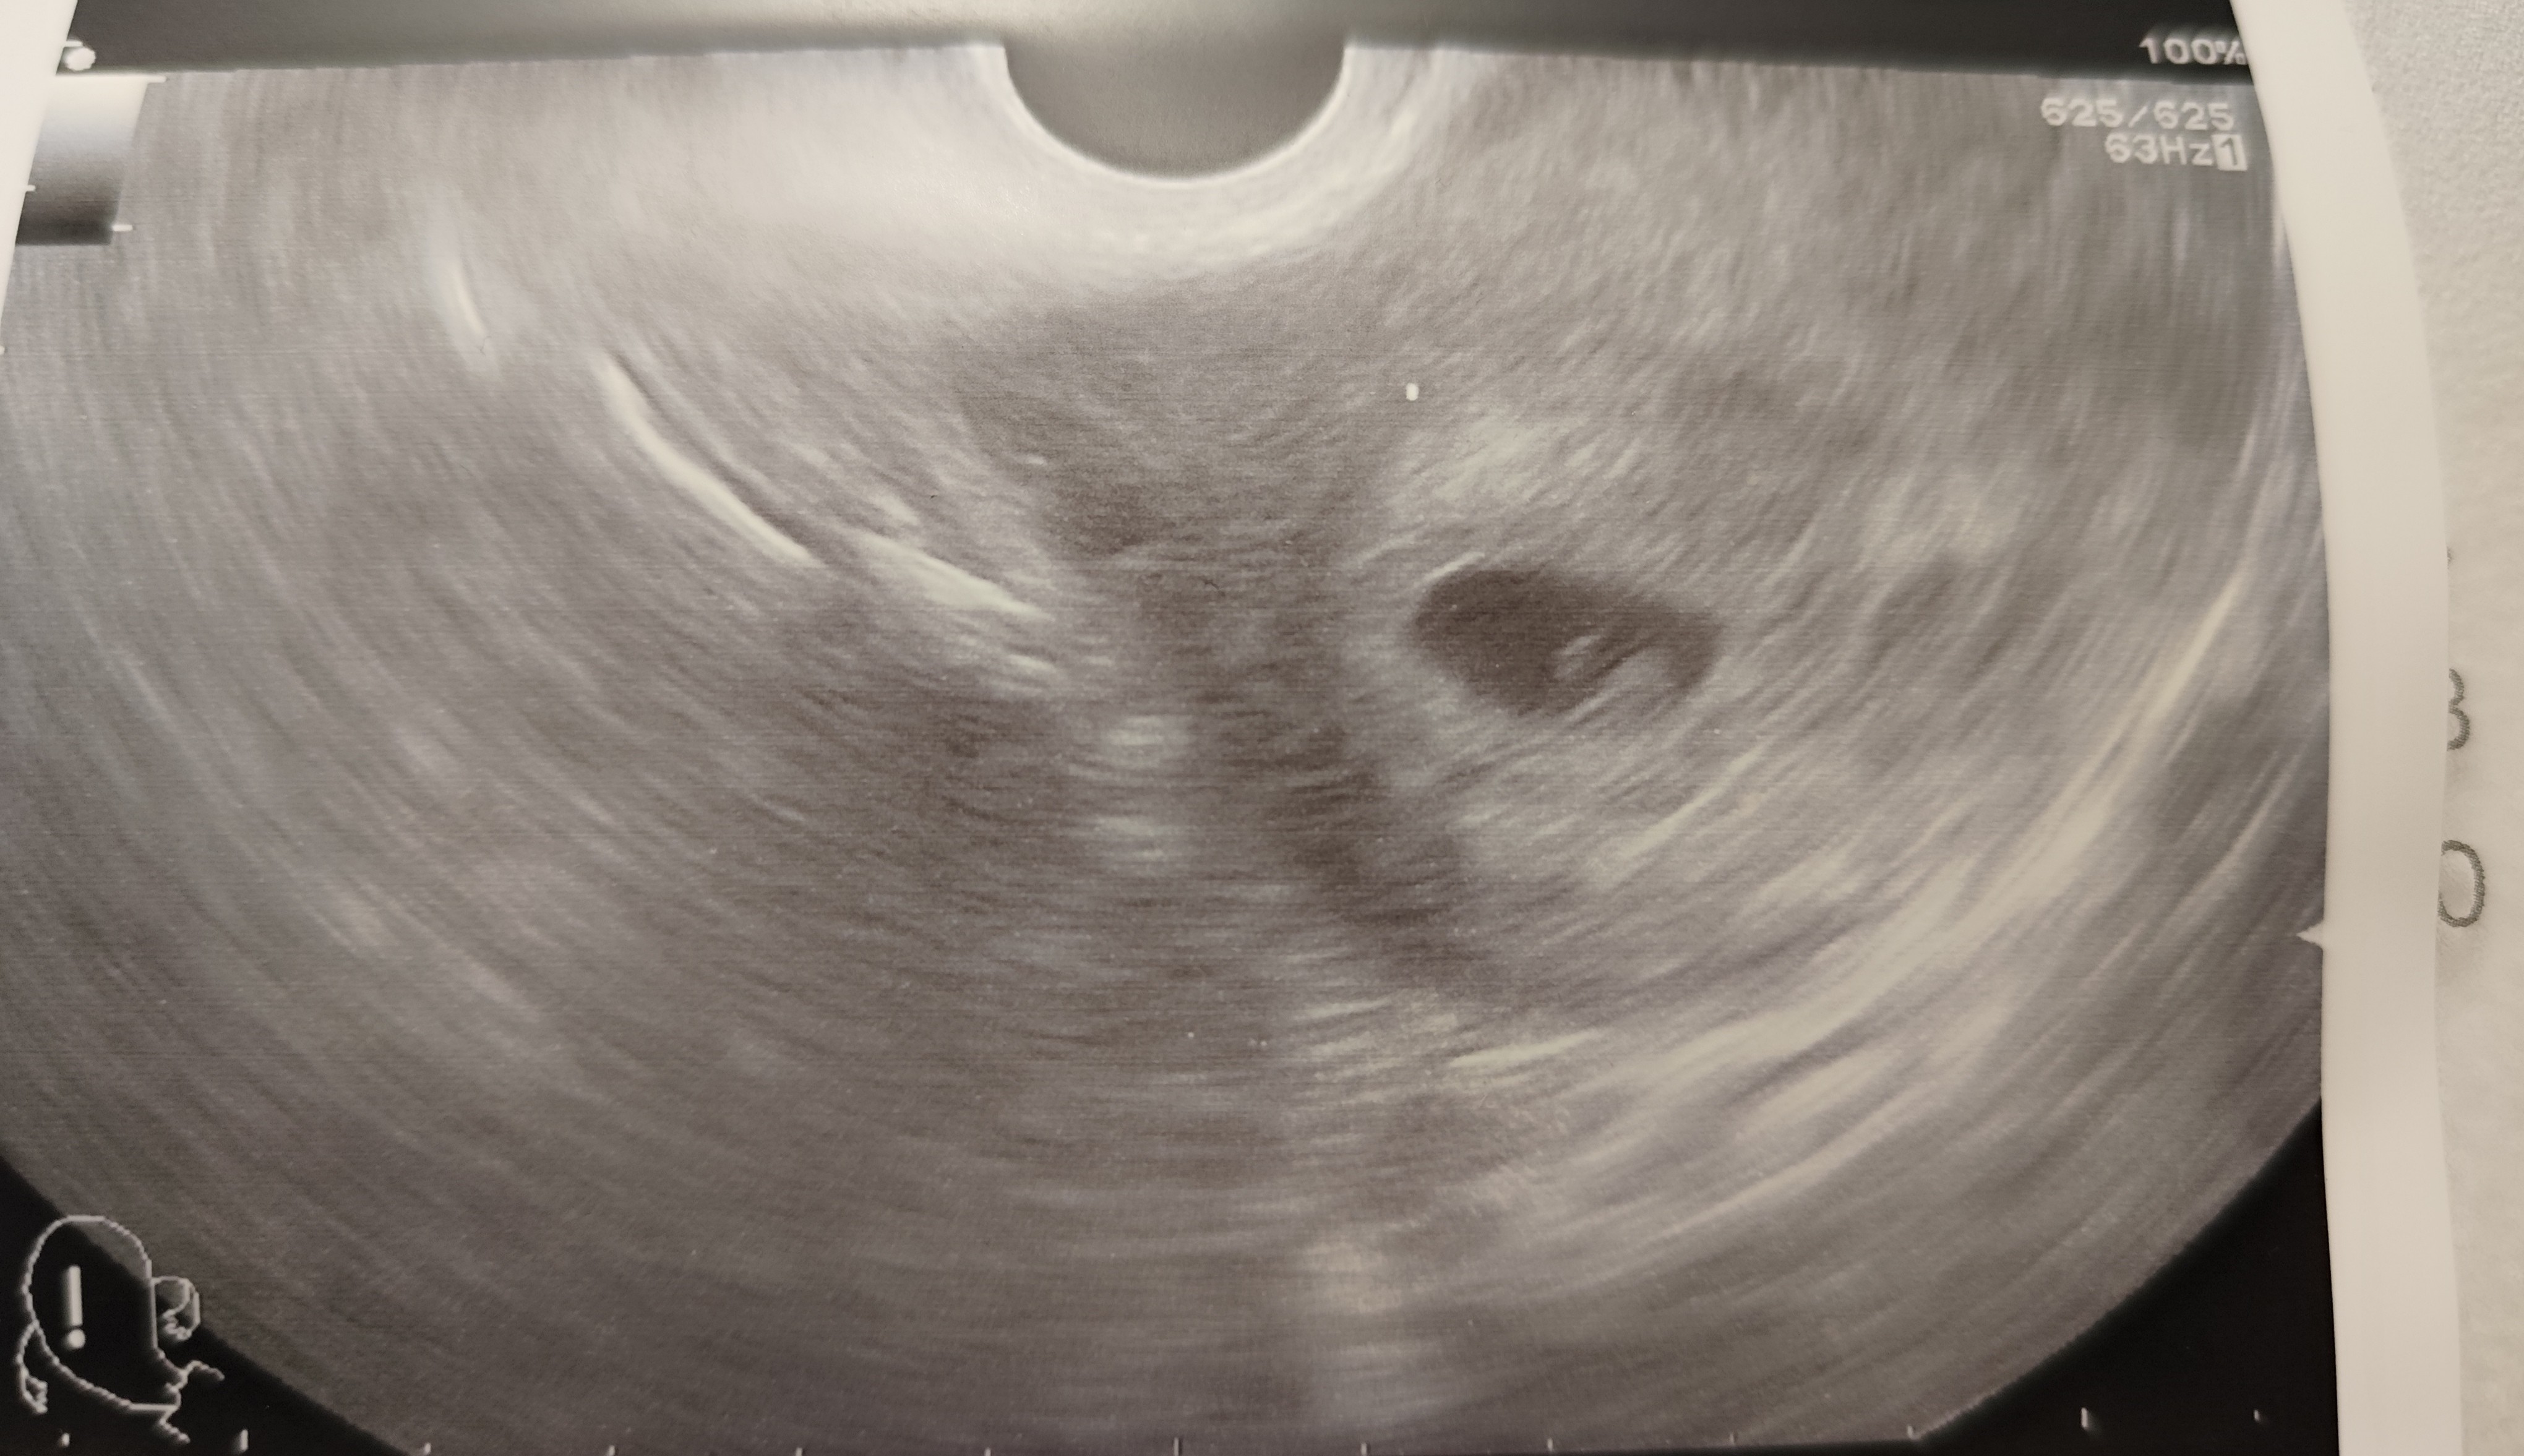

To nie ciąża bliźniacza ani jednojajowa ani dwujajowaDziewczyny pomóżcie jestem w 5/6 tyg lekarz powiedział że widzi jakaś przestrzen czy wy widzicie ciążę blizniacza ? Jeśli tak to w tym jednym pęcherzyku czyli jednojajowa czy ten cień to drugi pęcherzyk ?

wygląda na ciążę pojedynczaDziewczyny pomóżcie jestem w 5/6 tyg lekarz powiedział że widzi jakaś przestrzen czy wy widzicie ciążę blizniacza ? Jeśli tak to w tym jednym pęcherzyku czyli jednojajowa czy ten cień to drugi pęcherzyk ?

Dziękuje, bo lekarz coś zaczął mówić że może być ciąża bliźniacza, chyba miał słaby sprzęt ;p Nast wizyta u innego lekarza mam nadzieję że z lepszym sprzętem